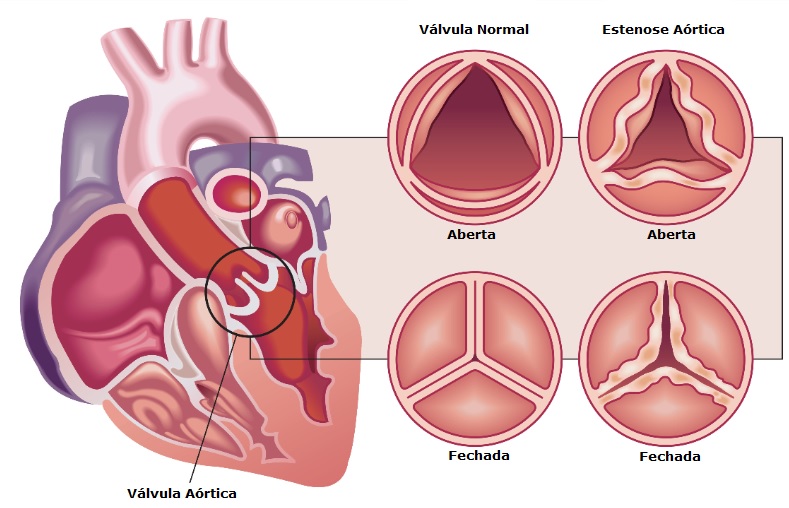

O que é estenose aórtica?

A válvula aórtica é uma das válvulas cardíacas que direcionam o fluxo de sangue através do coração para o resto do corpo. A estenose aórtica é quando a válvula torna-se espessa, endurecida ou inflamada. Isso pode começar como resultado de infecção (febre reumática), uma anormalidade congênita ou, em pessoas mais velhas, a válvula pode tornar-se calcificada com o tempo, isso causa movimento restrito dos folhetos valvares e fluxo sanguíneo ineficaz para o corpo e as artérias coronárias (as artérias que abastecem o coração com sangue). Devido a este fluxo sanguíneo restrito, as pessoas podem sentir sintomas como dor no peito, fadiga, falta de ar, tonturas e desmaios, retenção de líquidos ou capacidade de exercício reduzida.

Esses sintomas são muito importantes de serem identificados, pois, demonstram que a doença está em estado avançado e necessita de tratamento.